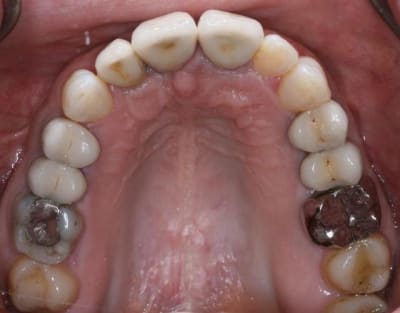

Bon finalement je vous poste le cas terminé.

La prochaine fois je ferrai une greffe d'apposition comme j'avais pu le préssentir... Ca me permettra de garder les papilles.

A la prochaine séance je gomme la coloration mésiale de 12, c'est promis ;+)

Un cas pas évident... l'important est que la patiente soit contente à la fin.